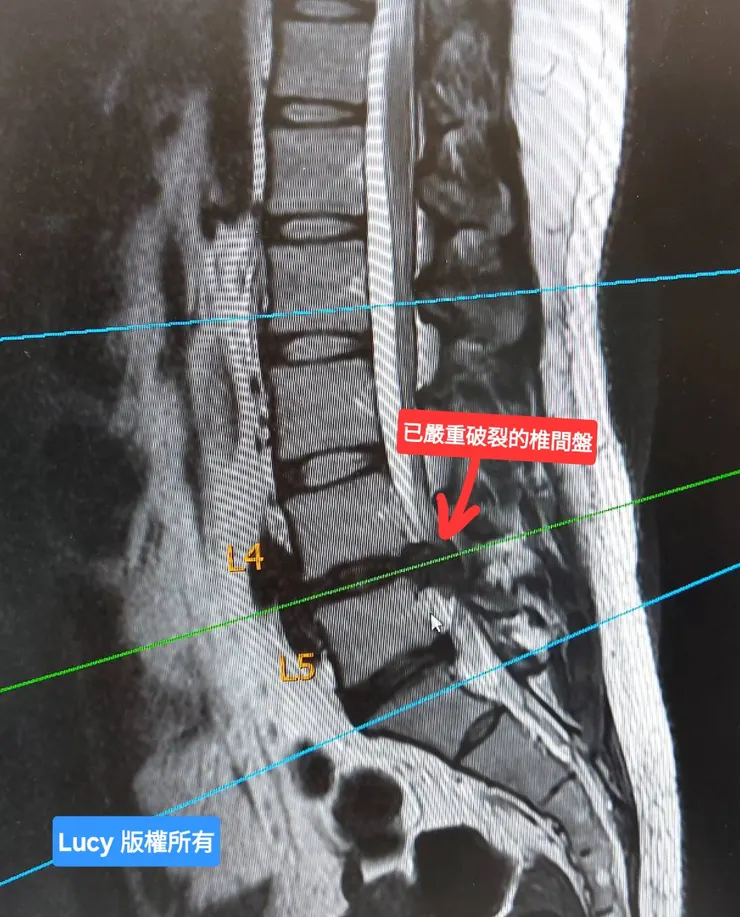

同時,媽媽也在和急診醫生反覆確認病情的嚴重性。感謝這位急診醫師,他依然耐心且親切地向媽媽和電話遠端的阿姨詳細說明:「我的椎間盤不只是突出,而是已經破裂,骨髓核嚴重壓迫到神經,真的必須馬上開刀。」。

核磁共振影像看到第4、5節椎間盤嚴重破裂

核磁共振影像看到第4、5節椎間盤嚴重破裂,已看不到白色脊髓